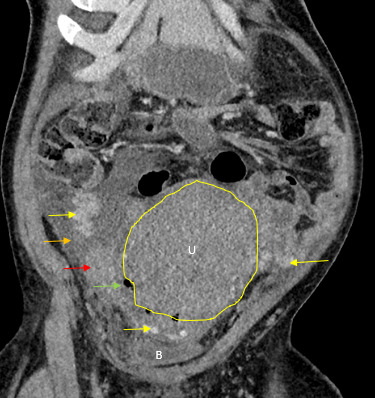

The initial impressions of the axial and coronal CT images revealed dilation of the right ovarian vein in addition to intraperitoneal fluid accumulation on the right side (Fig. 1-2). Portovenous and delayed phase images did not demonstrate contrast pooling or persistent hyperattenuation to suggest hyperacute hemorrhage (Fig. 3-4). Additionally, there was evidence of peritoneal air present between the uterine myometrium and ovarian vasculature most notable along the right aspect of the anterior inferior uterus. A contour abnormality along the right parasagittal lower uterine segment was also noted and interpreted as a uterine defect without signs of free intraperitoneal hemorrhage. In conjunction with her clinical picture, these radiologic findings raised our suspicion for a contained uterine rupture although there were no pathognomonic imaging findings to confirm an associated retroperitoneal hematoma. The patient was urgently taken to the operating room for an exploratory laparotomy to confirm the diagnosis and to manage surgically if indicated.

There was no evidence of hemoperitoneum upon abdominal entry. There was a minor 1 cm x 1 cm superficial serosal defect noted at the right cornua, which was hemostatic and secondary to manipulation of the uterus. Most notably, a large non-expanding right-sided broad ligament hematoma measuring 15 cm x 6 cm was noted extending into the retroperitoneal space over the site of suspected uterine rupture (Fig. 5-7). The patient remained hemodynamically stable intraoperatively, and following direct observation, the hematoma was noted to be non-expanding. The uterus was taken off tension, and the decision was made to close the patient without further intervention.

Uterine rupture was highly suspected even prior to the exploratory laparotomy due to the presence of air between the uterine myometrium and the ovarian vessels. Figures 1-4 describe CT findings consistent with uterine rupture. This is the first case report of a uterine rupture being managed conservatively similarly to previously described management options for contained uterine hematomas.

While the CT raised our suspicion for uterine rupture preoperatively, it did not predict for the size and extent of the broad ligament hematoma that we observed intraoperatively. It was appropriate to perform an exploratory laparotomy as most uterine ruptures require surgical management. The decision to manage conservatively rested on the non-expanding nature of the hematoma, an intact broad ligament, and the patient’s hemodynamic stability. As these safety checks were passed, we decided to conservatively manage the defect and to avoid the more morbid hysterectomy as well as its potential complications.